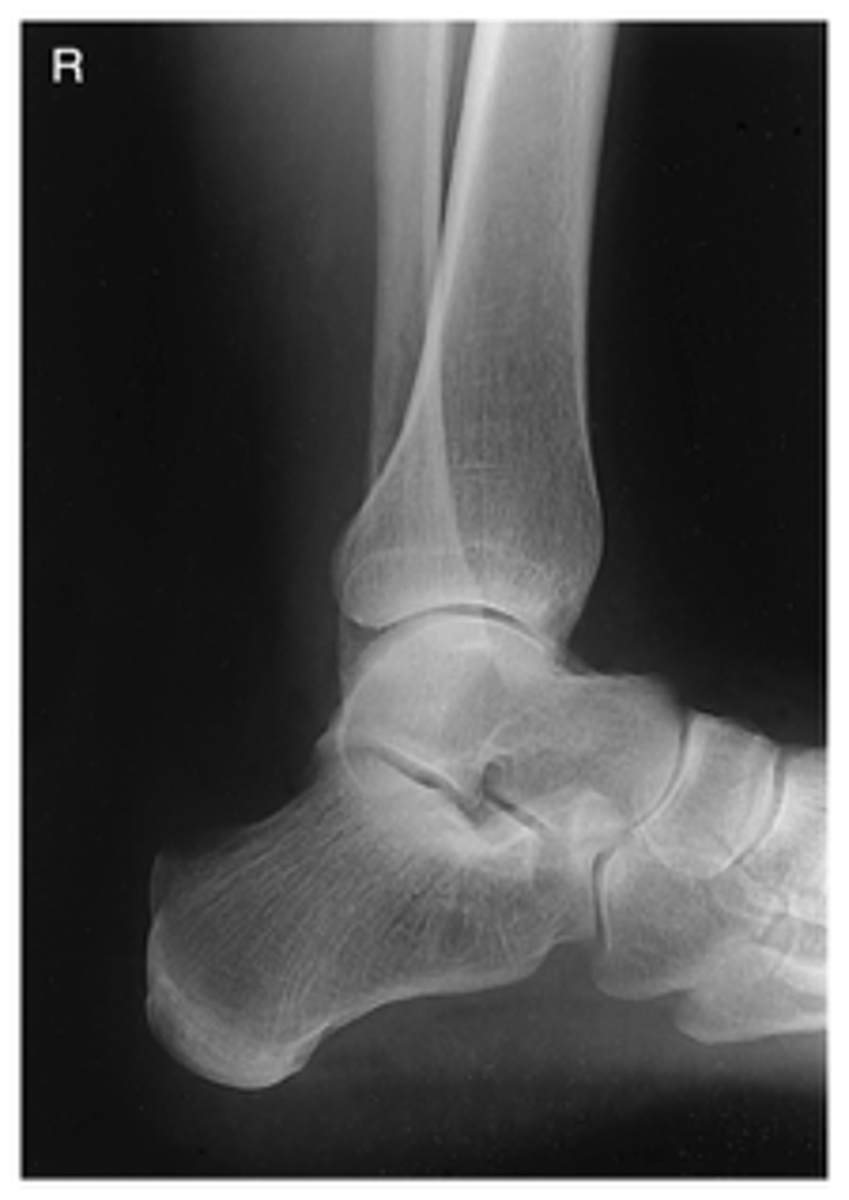

AP Ankle

What projection is this?

Evaluation Criteria AP Ankle

- AP

- CR midway between malleoli

- Distal ⅓ of tibia and fibula demonstrated

- Proximal ½ of metatarsals included

- Medial and superior aspect of ankle joint open

AP Mortise Ankle

Evaluation Criteria AP Mortise Ankle

- Intermalleolar line parallel to IR

- Ankle rotated 15-20 degrees medial rotation

- Entire ankle mortise open

- Optimal exposure factors